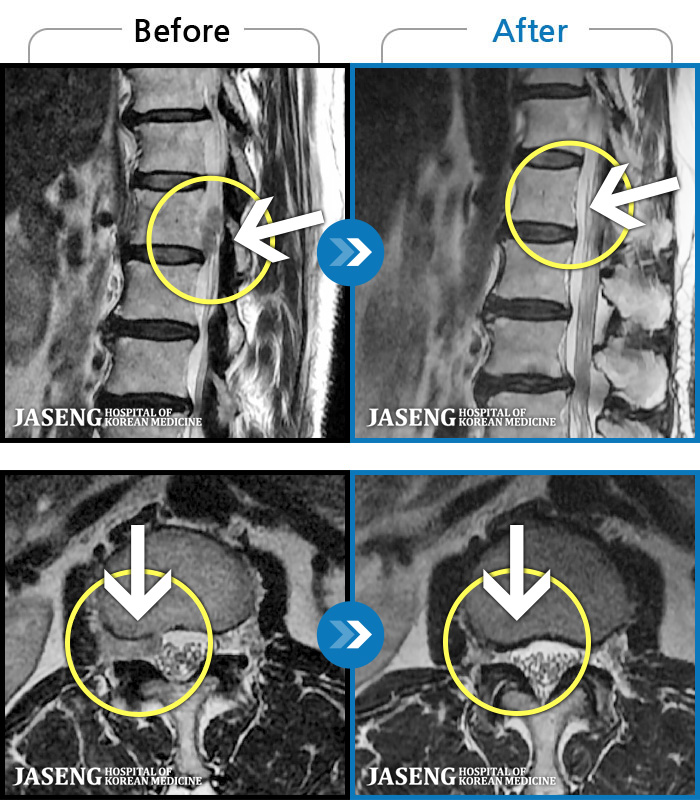

허리디스크

해운대 · 김상돈 원장

아래쪽 허리와 우측 골반에 통증이 있었습니다.

촬영시기

2019.08.26 ~ 2025.08.09

2025.08.14